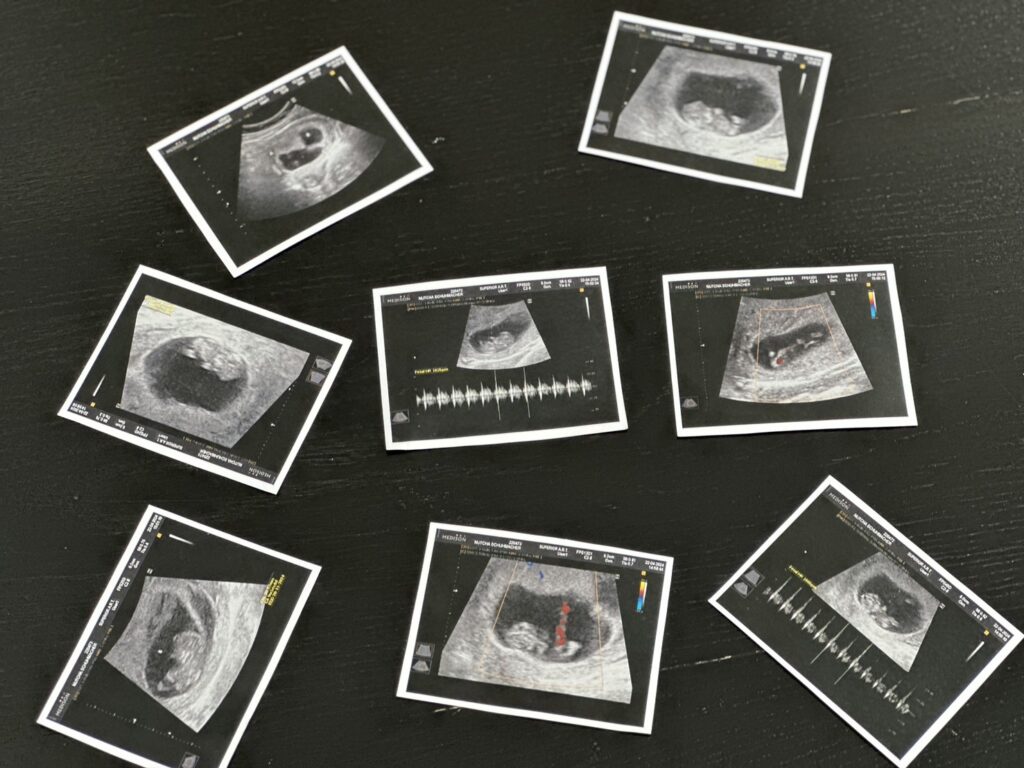

เป็นข่าวสุดปังไปตั้งแต่ปลายปีกับงานวิวาห์หวานสุดอลังการงานสร้างไม่นาน นางเอกสาวชื่อดัง ”นนนี่ ณัฐชา ชูมักเคอร์“ ภรรยาสาวหมาด ๆ ของ ”แอ็คมี่ วรวัฒน์ นาคแนวดี“ นักธุรกิจนักลงทุนระดับหมื่นล้าน และนักร้องนำวง DoubleDeep ที่ล่าสุดได้ลงรูปคู่ในไอจีในชุดสีขาวที่แอบให้เห็นท้องที่กำลังเริ่มใหญ่ขึ้น พร้อมประกาศข่าวดีว่าตอนนี้ นนนี่ กำลังตั้งท้องลูกคนแรกแล้ว และข้อความ “thank you for coming to my family . Love you baby #10weeks”